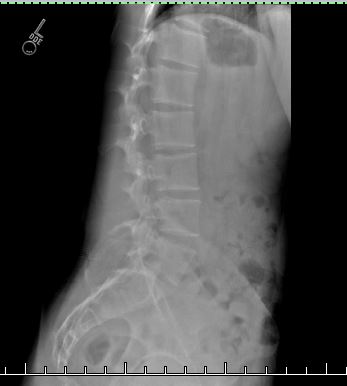

Are my low back muscles probably too tight/compressed or could it be something else? This is me lying down on my side and the curve is still there so what do I do?

X1